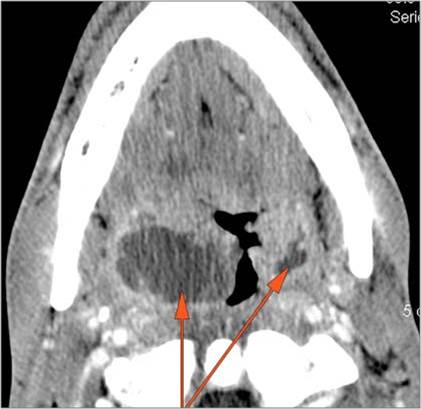

Cervical Lymph Nodes

There is reactive cervical lymphadenopathy. [Yes/No]

There is suppurative cervical lymphadenopathy. [Yes/No]

If there is suppurative cervical adenopathy the purulent material outside the lymph node(s) capsule(s). [Yes/No]